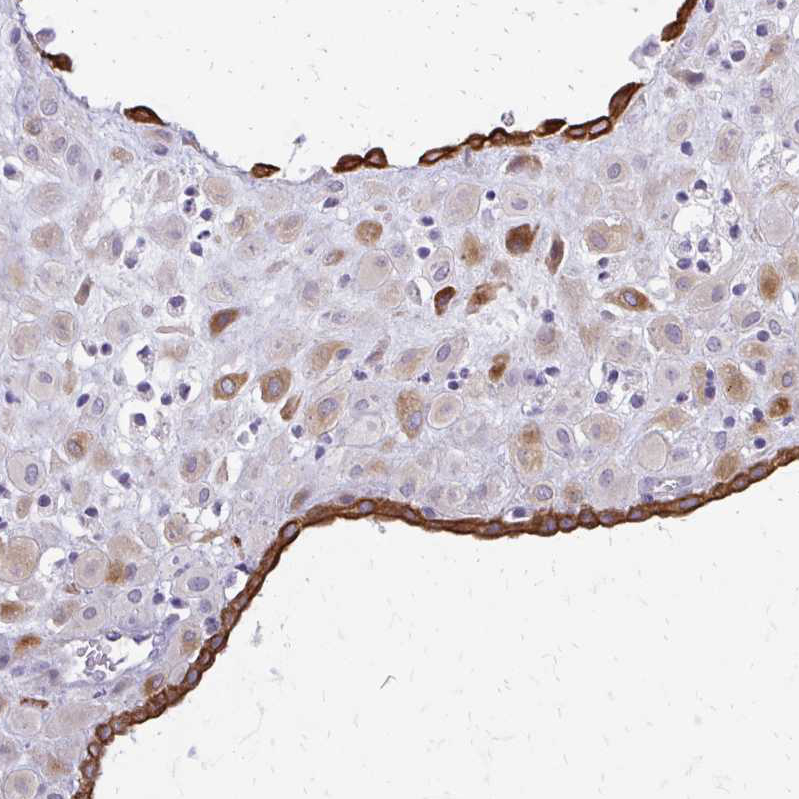

Immunohistochemical staining of human placenta shows moderate cytoplasmic positivity in decidual cells and strong positivity in trophoblast.